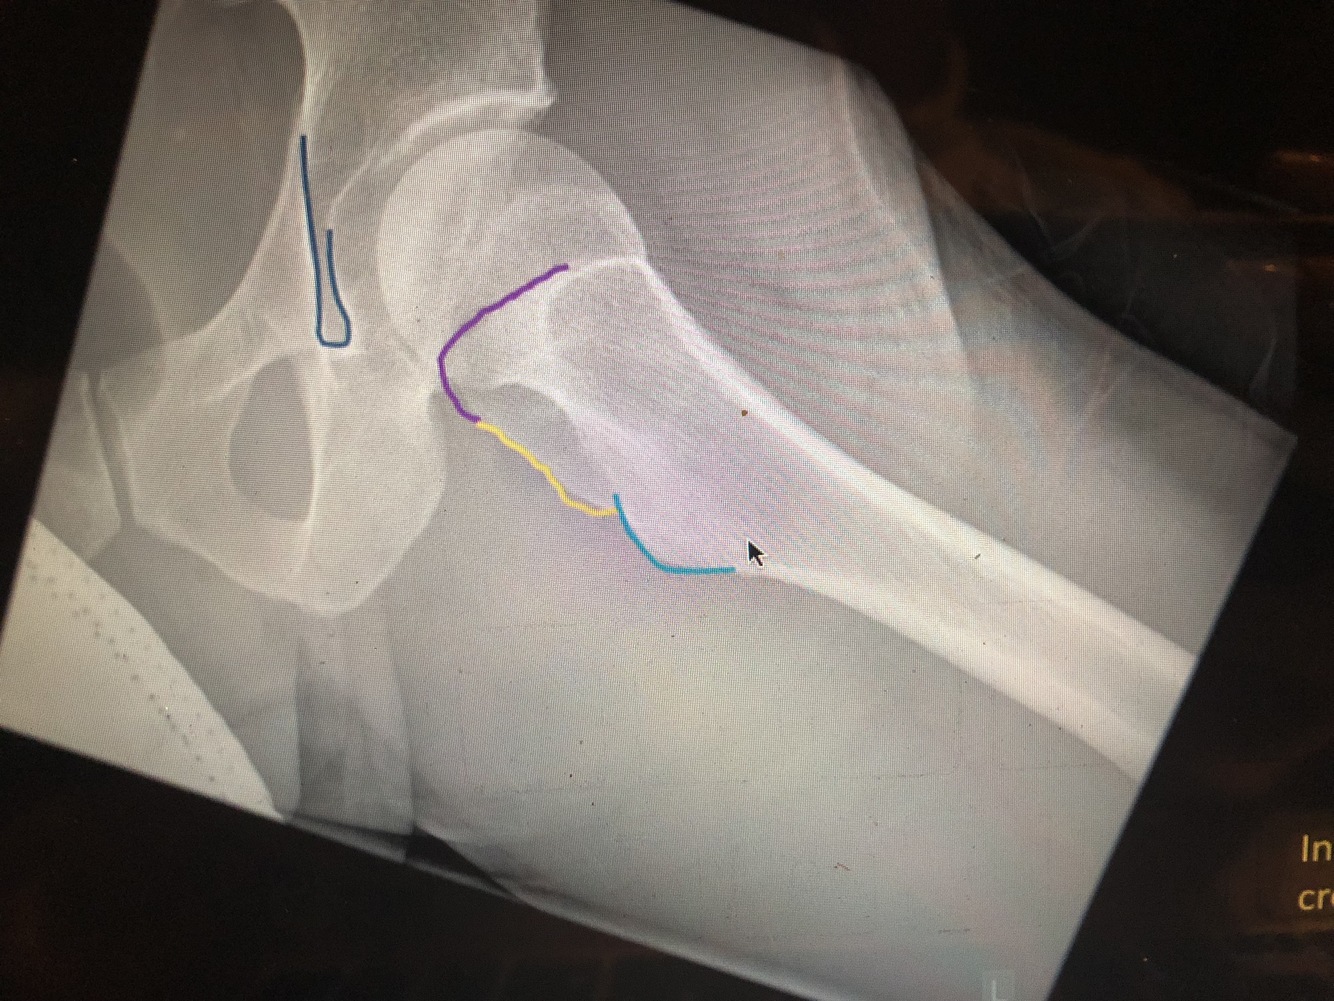

What is #1

lateral margin of femoral head

What is #2

medial margin of femoral head

What is #3

fovea centralis

What is #4

physeal line or scar

What is the blue line/#3?

secondary compressive trabeculae

What is the yellow line/#2?

primary tensile trabeculae

What is the blue area/#4

Ward’s triangle is the relatively trabeculae-free area